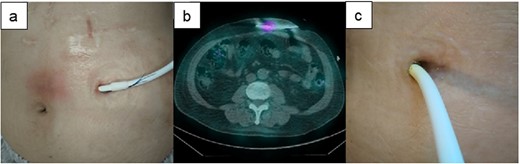

A 49-y-old woman with hypertrophic cardiomyopathy underwent LVAD implantation (HeartMate II™, Abbott Co., Abbott Park, IL, USA) and was readmitted to our institution for DLI 4.5 y after this implantation. Skin induration, tenderness along the driveline tunnel, and bleeding and purulent discharge from the driveline tunnel space were found; furthermore, the culture from driveline drainage showed Pseudomonas aeruginosa (Fig. 5a). Although surgical relocation of the DLES was considered, 67Ga SPECT showed a high signal up to 5 cm inside the DLES (Fig. 5b), and the range of cutaneous infection was limited to 5 cm from the site. Therefore, the catheter cleaning method paired with intravenous antibiotics was selected. Consequently, the exuded solution became clear, and the amount gradually decreased. The patient’s DLI gradually improved (Fig. 5c), and she was discharged from our hospital on day 57 after hospitalization.

The clinical course of development of the DLI in Case 3. (a) Skin induration and tenderness along the driveline tunnel and bleeding and purulent discharge from the driveline tunnel space were found. (b) 67Ga SPECT suggested a high signal up to 5 cm inside the DLES. (c) The exuded solution became clear, and the amount gradually decreased. The patient’s DLI gradually improved.